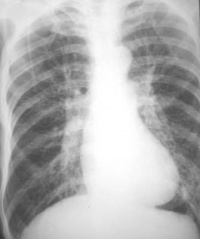

一、X线检查:胸廓扩张,肋间隙增宽肋骨平行,活动减弱,膈降低且变平,两肺野的透亮度增加。

诊断根据病史、体检、X射线检查和肺功能测定可以诊断科研。X射线检查表现为胸腔前后径增大,胸骨前突,胸骨后间隙增宽,横膈低平,肺纹理减少,肺野透光度增加,悬垂型心脏,肺动脉及主要分支增宽,外周血管细小。肺功能测定表现为残气、肺总量增加、残气/肺总量比值增高、1秒率显著降低、弥散功能减低。